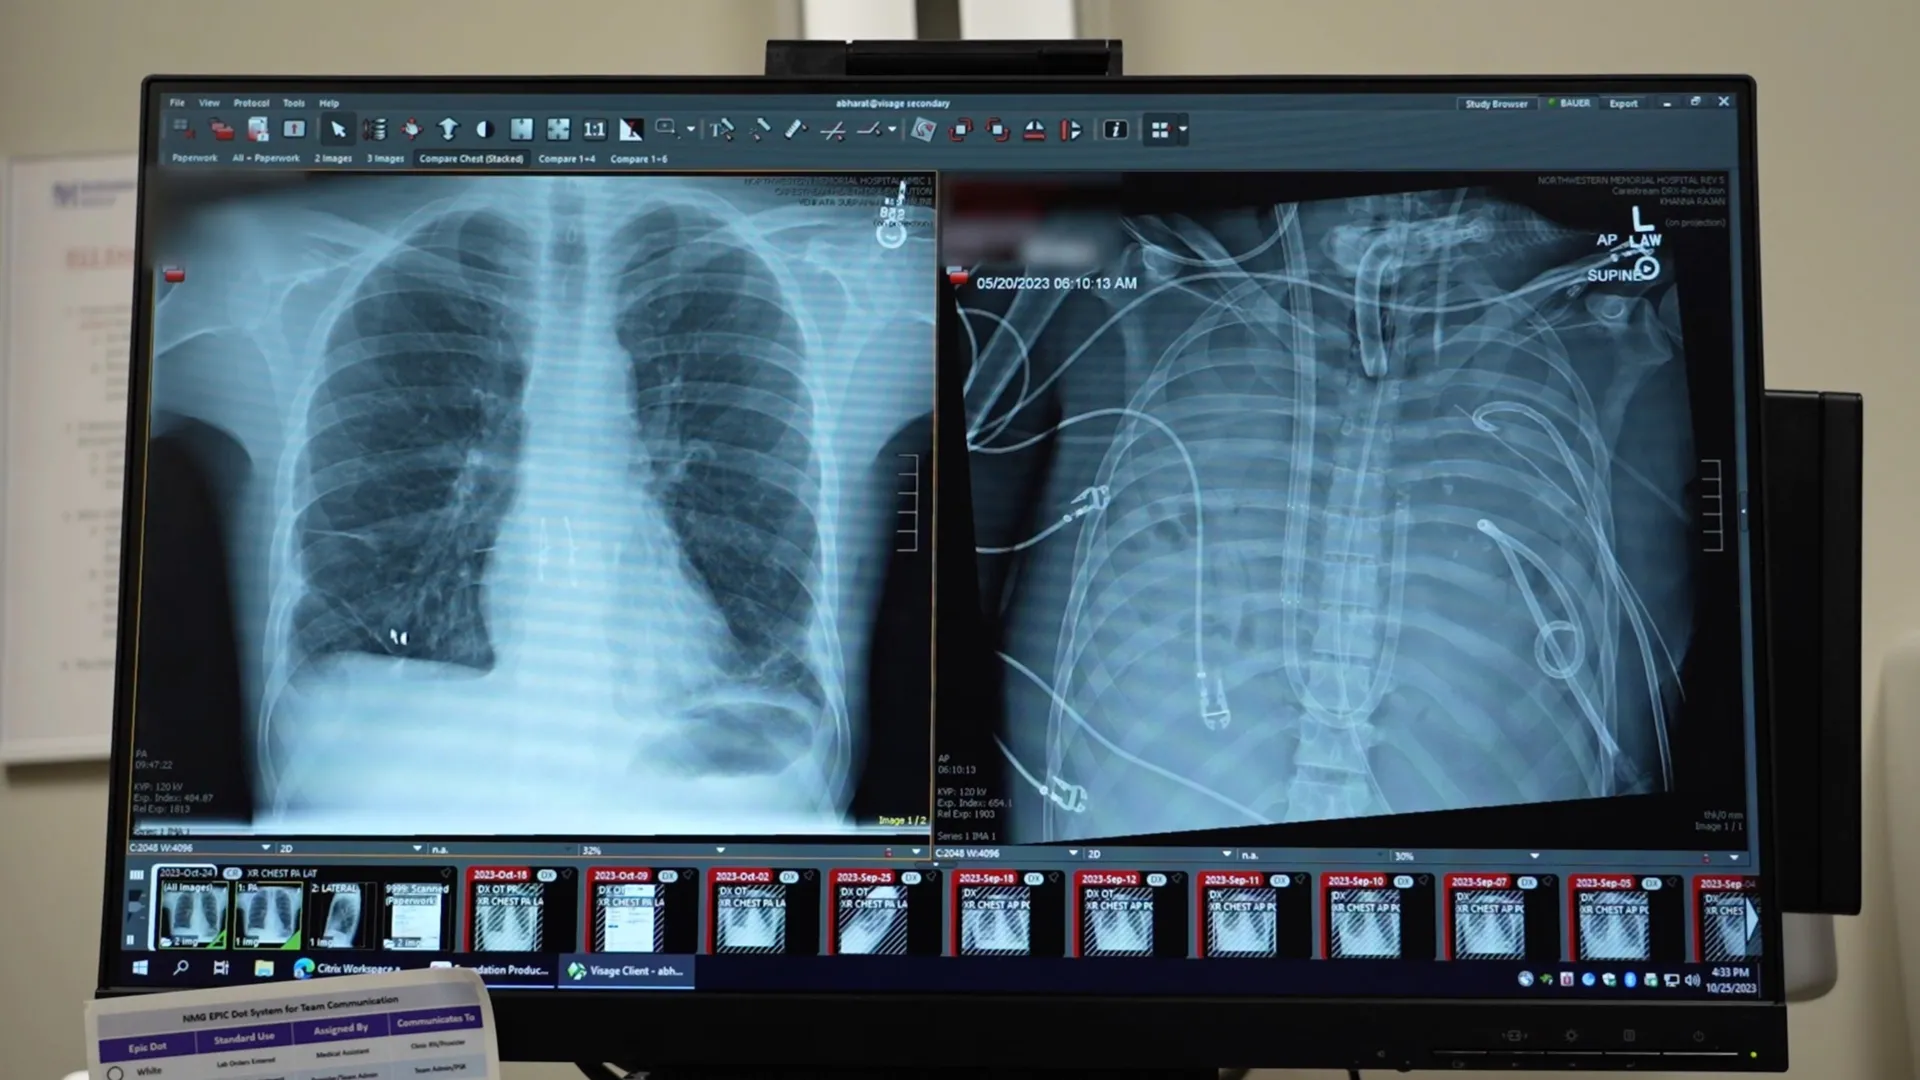

Dr. Ankit Bharat, a thoracic surgeon at Northwestern University and lead author of the study, described the patient’s initial presentation as critically ill. "His heart stopped as soon as he arrived. We had to perform CPR," Dr. Bharat stated. "When the infection is so severe that the lungs are melting, they’re irrecoverably damaged. That’s when patients die." This grim assessment highlighted the advanced stage of his illness, where the lungs were not only failing to function but were actively contributing to a systemic infection that threatened to consume his entire body.

The interconnectedness of the heart and lungs presents a formidable obstacle in cases of complete lung removal. "The heart and lungs are intrinsically connected," Dr. Bharat explained. "When there are no lungs, how do you keep the patient alive?" To overcome this seemingly insurmountable hurdle, the medical team devised and implemented a sophisticated artificial lung system. This device was engineered to perform the essential functions of healthy lungs, including oxygenating the blood and removing carbon dioxide. Crucially, it also provided support for circulation, ensuring that the heart and other vital organs continued to receive the necessary oxygenated blood to function.

This artificial lung system acted as a temporary, external respiratory and circulatory support mechanism. It was integrated into the patient’s circulatory system, drawing deoxygenated blood, infusing it with oxygen, removing waste carbon dioxide, and returning the now oxygenated blood to the body. This allowed the patient’s failing organs, particularly the heart, to recover from the immediate shock of the infection and the stress of CPR.